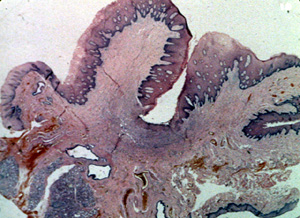

Esta

microfotografía de baja resolución

ilustra bien el aspecto lobulado de la lesión. Hay una

invaginación profunda en la porción central en que la pestaña de la

dentadura postiza fue localizada. |

| Este

microfotografía se observa el área ulcerada en la base de la

invaginación y muestra exudado inflamatorio, tejido fibroso reactivo y tejido de granulación.

| Periférico a

la ulceración el tejido del tipo predominante que comprende la mayoría

de la lesión, es el tejido conjuntivo fibroso bastante denso con un número

moderado de los vasos sanguíneos. Note la inflamación crónica

perivascular tan común en

las lesiones reactivas. Los fibroblastos son uniformes a lo largo hay

considerable colágeno denso. Con esta microfotografía usted

puede determinar que la única forma de eliminar la lesión es con la

biopsia por escisión. |